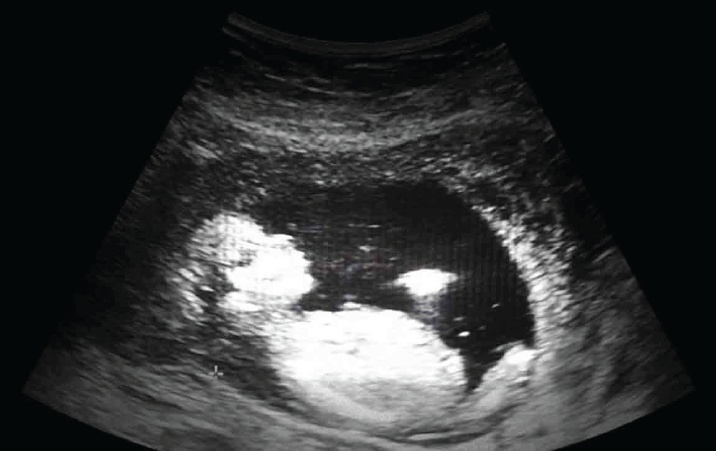

Ultrasound imaging technique is used to capture real-time images inside the human body. It has a wide range of clinical applications in diagnosis and treatment of medical conditions. The technique is widely used to diagnose the cause of pain, swelling and infection in internal organs and to examine foetus in pregnant women.

The team claims to have developed a new beamforming technique, which is demonstrated to outperform other existing techniques and yields the best image resolution throughout the field of view. The findings of their research have been published in a peer-reviewed journal Scientific Reports.

The researchers claimed that the developed F-DowMAS technique can improve both resolution and contrast of an image simultaneously and parallelly it can also reduce noise levels to a greater extent in the reconstructed image.